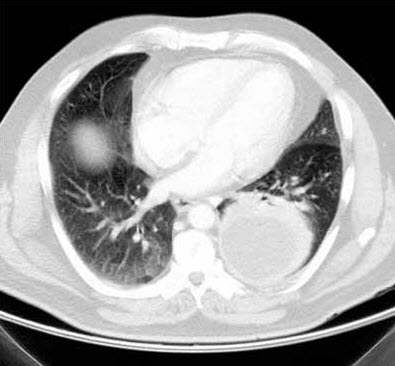

The posteroanterior chest radiograph suggests a rounded retrocardiac density in the left hemithorax (Figure 1). This is confirmed by the lateral view, which shows a large posterior lobulated shadow (Figure 2). The differential diagnosis at this point includes loculated pleural effusion, lung abscess without an air-fluid level, and thoracic empyema with or without an underlying malignancy. A chest CT scan delineates a 9 3 8-cm rounded density (Figure 3). The difference in homogeneity suggests a walled-off fluid collection with no evidence of air.

Intravenous levofloxacin and clindamycin are initiated in anticipation of percutaneous chest tube insertion into the lesion in the left hemithorax. The pleura in the left posterior lung base is slightly thickened; however, there is no evidence of an endobronchial obstructing lesion, hilar-mediastinal mass lesion, or pulmonary nodule. After the tube is placed, about 850 mL of foul-smelling brown fluid is evacuated by gravity (Figure 4). Microbiologic culture of the contents reveals Streptococcus intermedius, which is sensitive to levofloxacin. Cytologic analysis of the drainage material reveals no malignancy. Intravenous levofloxacin is continued for 10 days, followed by oral levofloxacin for another 2 weeks. Chest radiography and chest CT are repeated just before the chest tube is removed to assess whether surgery is needed. The CT scan shows almost complete resolution of the empyema.